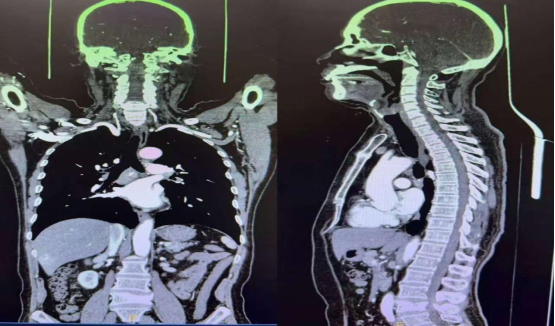

为不断满足广大患者对精准、高效、舒适医疗服务的需求,持续提升医学影像诊疗技术水平,精河县人民医院放射科近期在自治区人民医院专家指导下成功开展了“一次性头颈胸腹部联合增强CT扫描”影像检查技术。

核心优势:一是一次注射,全身成像。通过优化扫描方案和精确控制对比剂注射速率与扫描触发时机,实现在一次对比剂注射后,连续、快速地一次性完成从头部到腹盆腔的全范围增强扫描。极大地减少了患者的检查等候和扫描时间,尤其为危急重症患者赢得了宝贵的诊断时间。二是窗宽窗位智能联动,影像质量同步优化。以往分开扫描时,头部与胸腹部因组织密度差异大,需要采用完全不同的“窗宽窗位”参数进行图像后处理观察,操作繁琐且可能存在信息衔接误差。新技术配备先进的图像后处理平台,能够在一次性采集的容积数据基础上,智能、自动地分别适配并同步生成针对颅脑、肺窗、纵隔窗、腹部窗等不同部位的最佳观察图像。确保每一部位的影像都达到诊断最优标准,且所有图像源于同一时间点的同一套数据,对比性、一致性无可比拟。三是辐射剂量科学控制。得益于扫描流程的优化和新型迭代重建技术的应用,在获得更全面、更连贯诊断信息的同时,我们对扫描参数进行了个性化、精细化调控,确保总辐射剂量得到有效管理和控制,符合辐射防护最优化原则。

临床意义。一是对于急重症患者(如多发伤、疑似主动脉夹层、急性肺栓塞等):能快速进行全身评估,一次性排查多系统危重病变,为急诊抢救提供快速、全面的决策依据。二是对于肿瘤患者:在进行肿瘤分期、疗效评估或随访时,能够更准确地显示原发灶、淋巴结转移及远处脏器的转移情况,尤其有利于判断不同部位病灶的血供特点及其在相同增强时相的表现。此项技术的开展,既有效节省了肿瘤随访患者的检查时间,又减轻了经济负担。三是对于需要全身性疾病筛查或诊断不明的患者:提供了高效、全面的检查选择,有助于发现隐匿性病灶,避免因分次检查可能导致的病灶遗漏或延迟诊断。